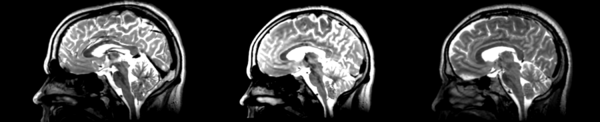

- 01053-t2 -> 01031-t2 = Result. All the images shown have the moving image on the left, the resultant image in the middle, and the target image on the right.

Rigid

01053>01031rigid.png = not bad... different brains of different sizes, but seem to be aligned in the ventricles so output seems okay. output slightly blurry. bad initial leveling displays.

Linear

01053>01031linear.png = not bad... different brains of different sizes, but seem to be aligned in the ventricles so output seems okay.output slightly blurry. bad initial leveling displays.

Affine

01053>01031_affine.png = looks good in terms of size. odd warping of frontal lobe and cerebellum area, but otherwise good coregistration.